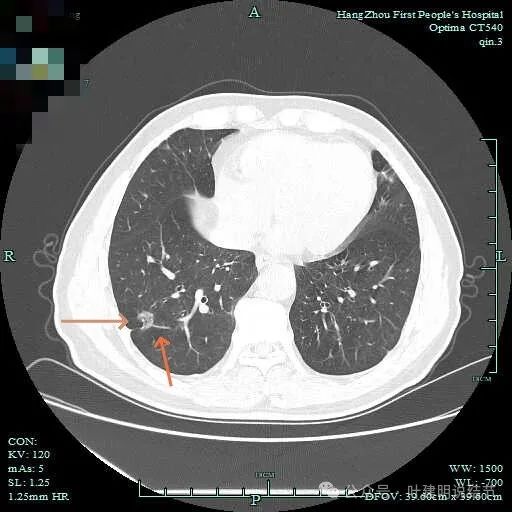

右下脊柱旁怎么也像有磨玻璃结节?但此处正常CT也是略显有慢性炎似的征象的,可这个病人明显结节状,还表面有细毛刺似的。

次病灶连续层面观察:

紧贴脊柱处混合密度,趴在脊柱上,这不像结节状。

但有小血管似的,磨玻璃部分界限较清。但此类异常影像在正常人的CT上也挺常见。

密度较高,确实像血管进入。但病灶片状,趴在脊柱上。

此层显得更呈小片状了。

与脊柱间似乎有间隙在,另见微小血管进入这条索状的偏高密度影处。

有细小血管进入,但说不上异常增粗。病灶仍是小片状,条状。

磨玻璃成分密度淡且界欠清,整体就是条索状弯曲的。

上图见细毛刺明显。

病灶实性伴细毛刺,与脊柱间有间隙在。